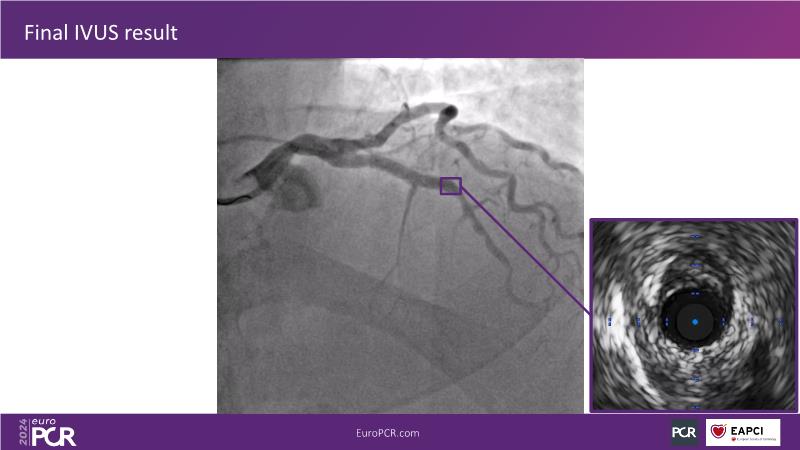

Explore this session to uncover the common association between calcium and acute coronary syndrome, and how intravascular lithotripsy (IVL) offers a safe solution for calcified lesions, with comparable procedural success rates. However, note that ACS cases involving calcium may lead to higher major adverse cardiac events (MACE). Special attention is warranted for women due to their propensity for adverse outcomes. Discover how the C2 + IVL catheter enhances procedural flexibility, yet high intracoronary imaging rates did not yield differences in MACE. Additionally, learn about the potential role of IVL in treating in-stent restenosis (ISR).

- To share clinical experience to uncover practical tips and techniques for intravascular lithotripsy in complex calcified lesions